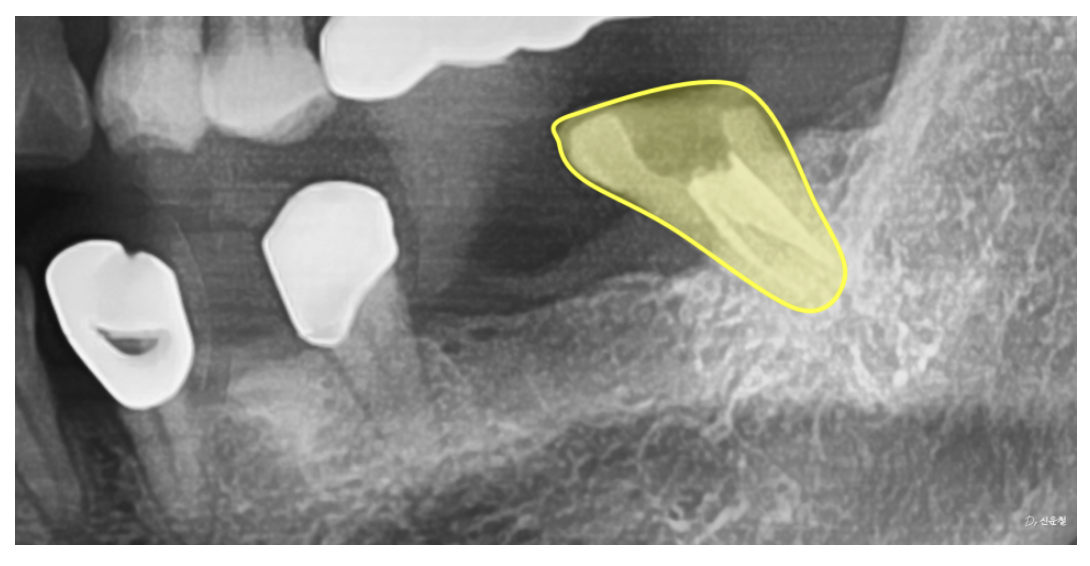

④ 오래된 보철물 내부 손상

오래 사용한 보철물(크라운)은

겉으로 멀쩡해 보여도

작은 틈이나 구멍으로 음식물과 세균이 침투할 수 있습니다.

이 경우 시간이 지나면

안쪽 치아가 다시 약해지며

충치·염증이 발생할 위험이 큽니다.

5단계: 오래된 보철물 제거 후 내부 상태 확인

보철물 표면만 보고 판단하면 안 됩니다.

X-ray로도 안쪽이 명확히 보이지 않기 때문에

보철물을 제거해 내부 충치·염증 여부를 직접 확인했습니다.

일부 치아는 세균이 뿌리까지 퍼져 신경치료

일부는 내부 충치 제거 후 새 보철물 제작

신경치료만 되어 있던 어금니는 크라운으로 보호